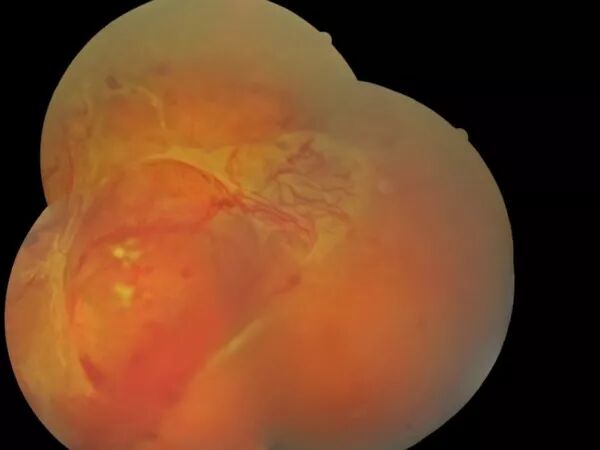

La DMLA humide ou exsudative

Elle correspond à la formation de nouveaux vaisseaux anormaux dits "néo-vaisseaux" sous la rétine. La structure anormale de ces vaisseaux fait que leur paroi laisse diffuser du sérum responsable d’un soulèvement de la rétine, et/ou du sang. L'évolution est rapide et se manifeste par des métamorphopsies "déformations" des lignes droites et une baisse de vue.

Le traitement par agents anti-angiogéniques doit être instauré le plus rapidement possible et est administré directement dans l'oeil par injections intravitréennes au cabinet de l'ophtalmologiste